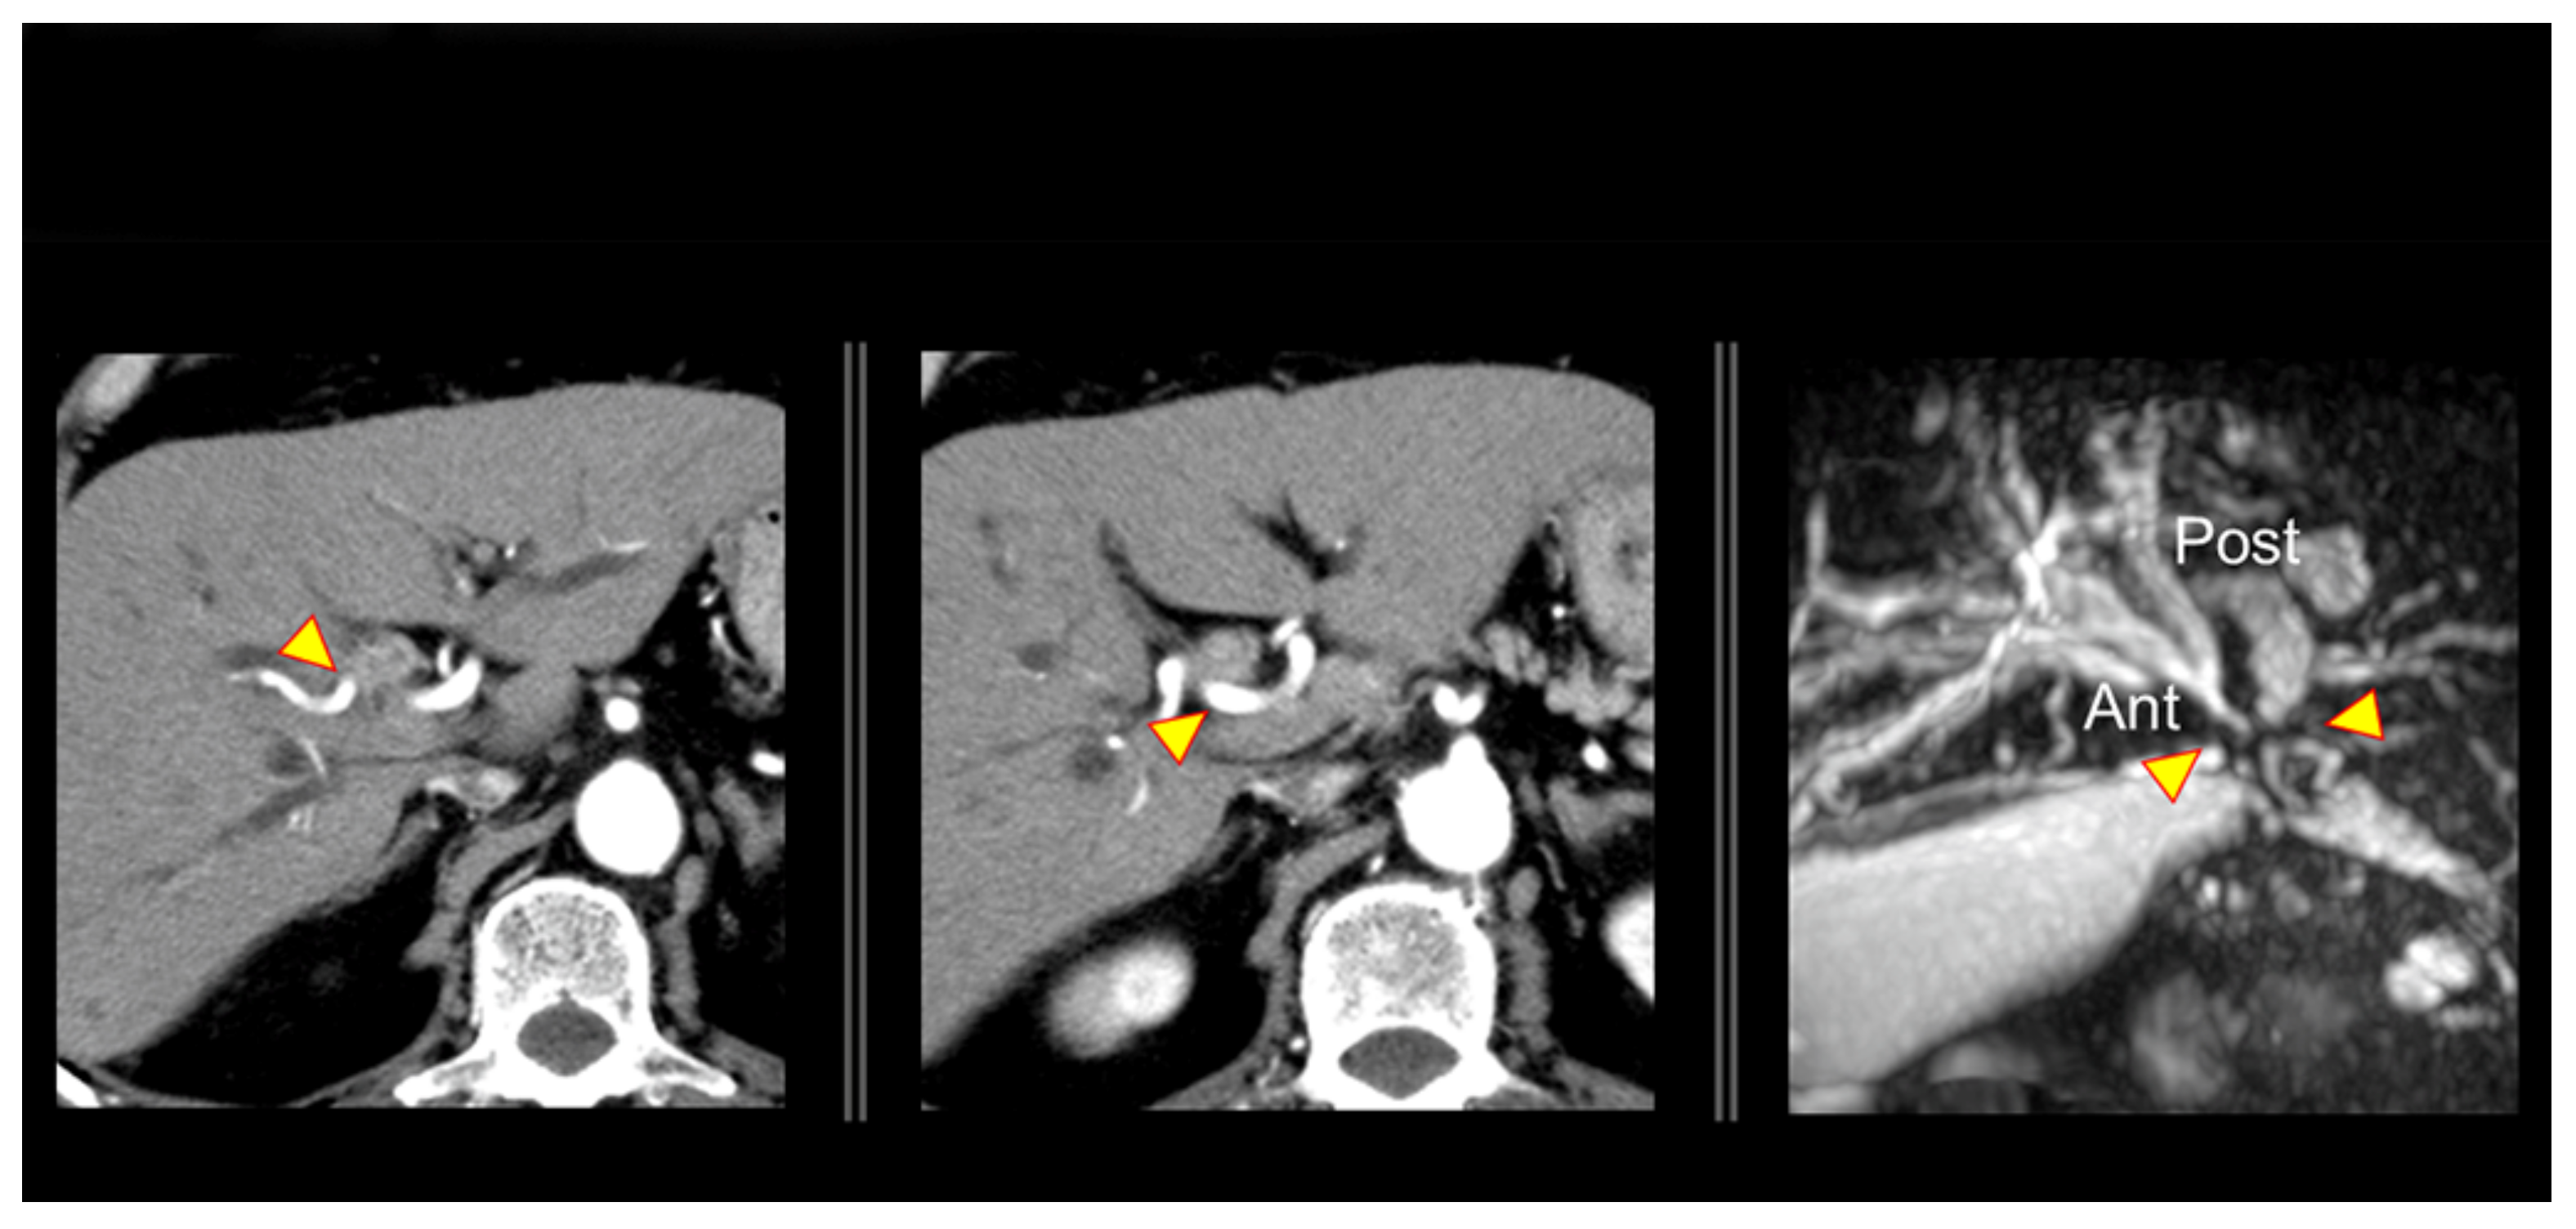

2. Anatomical Features of the Hepatic Hilum and Hepatic Artery